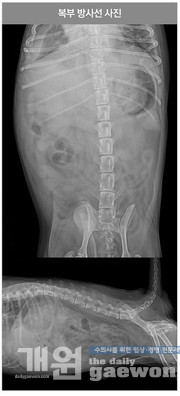

흉부 방사선 촬영상 흉수와 심비대증이 확인 되었으며, 복부 방사선 촬영상 뚜렷한 간비대증 및 복수 소견이 보였다.

복부 초음파 검사상 간비대증, 간에코상승, 우측 부신 크기 증가의 소견을 보였다. 심장 정밀초음파 검사상 심방 수축과 심실 수축의 일치하지 않음을 확인했다. 심장박동수는 분당 40~50회 정도를 지속적으로 유지하였다.